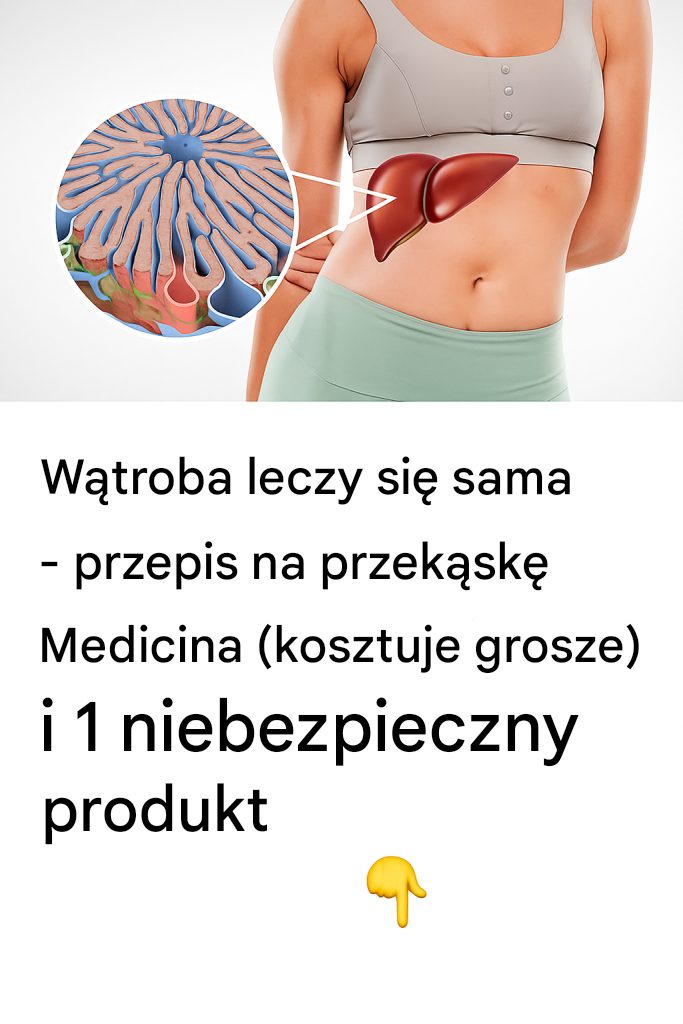

Czasami nasze ciało daje nam subtelne ostrzeżenie, zanim sprawi, że poczuje się głośniej. Zmęczenie, małe, krótkotrwałe bóle i dolegliwości, które przypisujemy rutynie… A co…